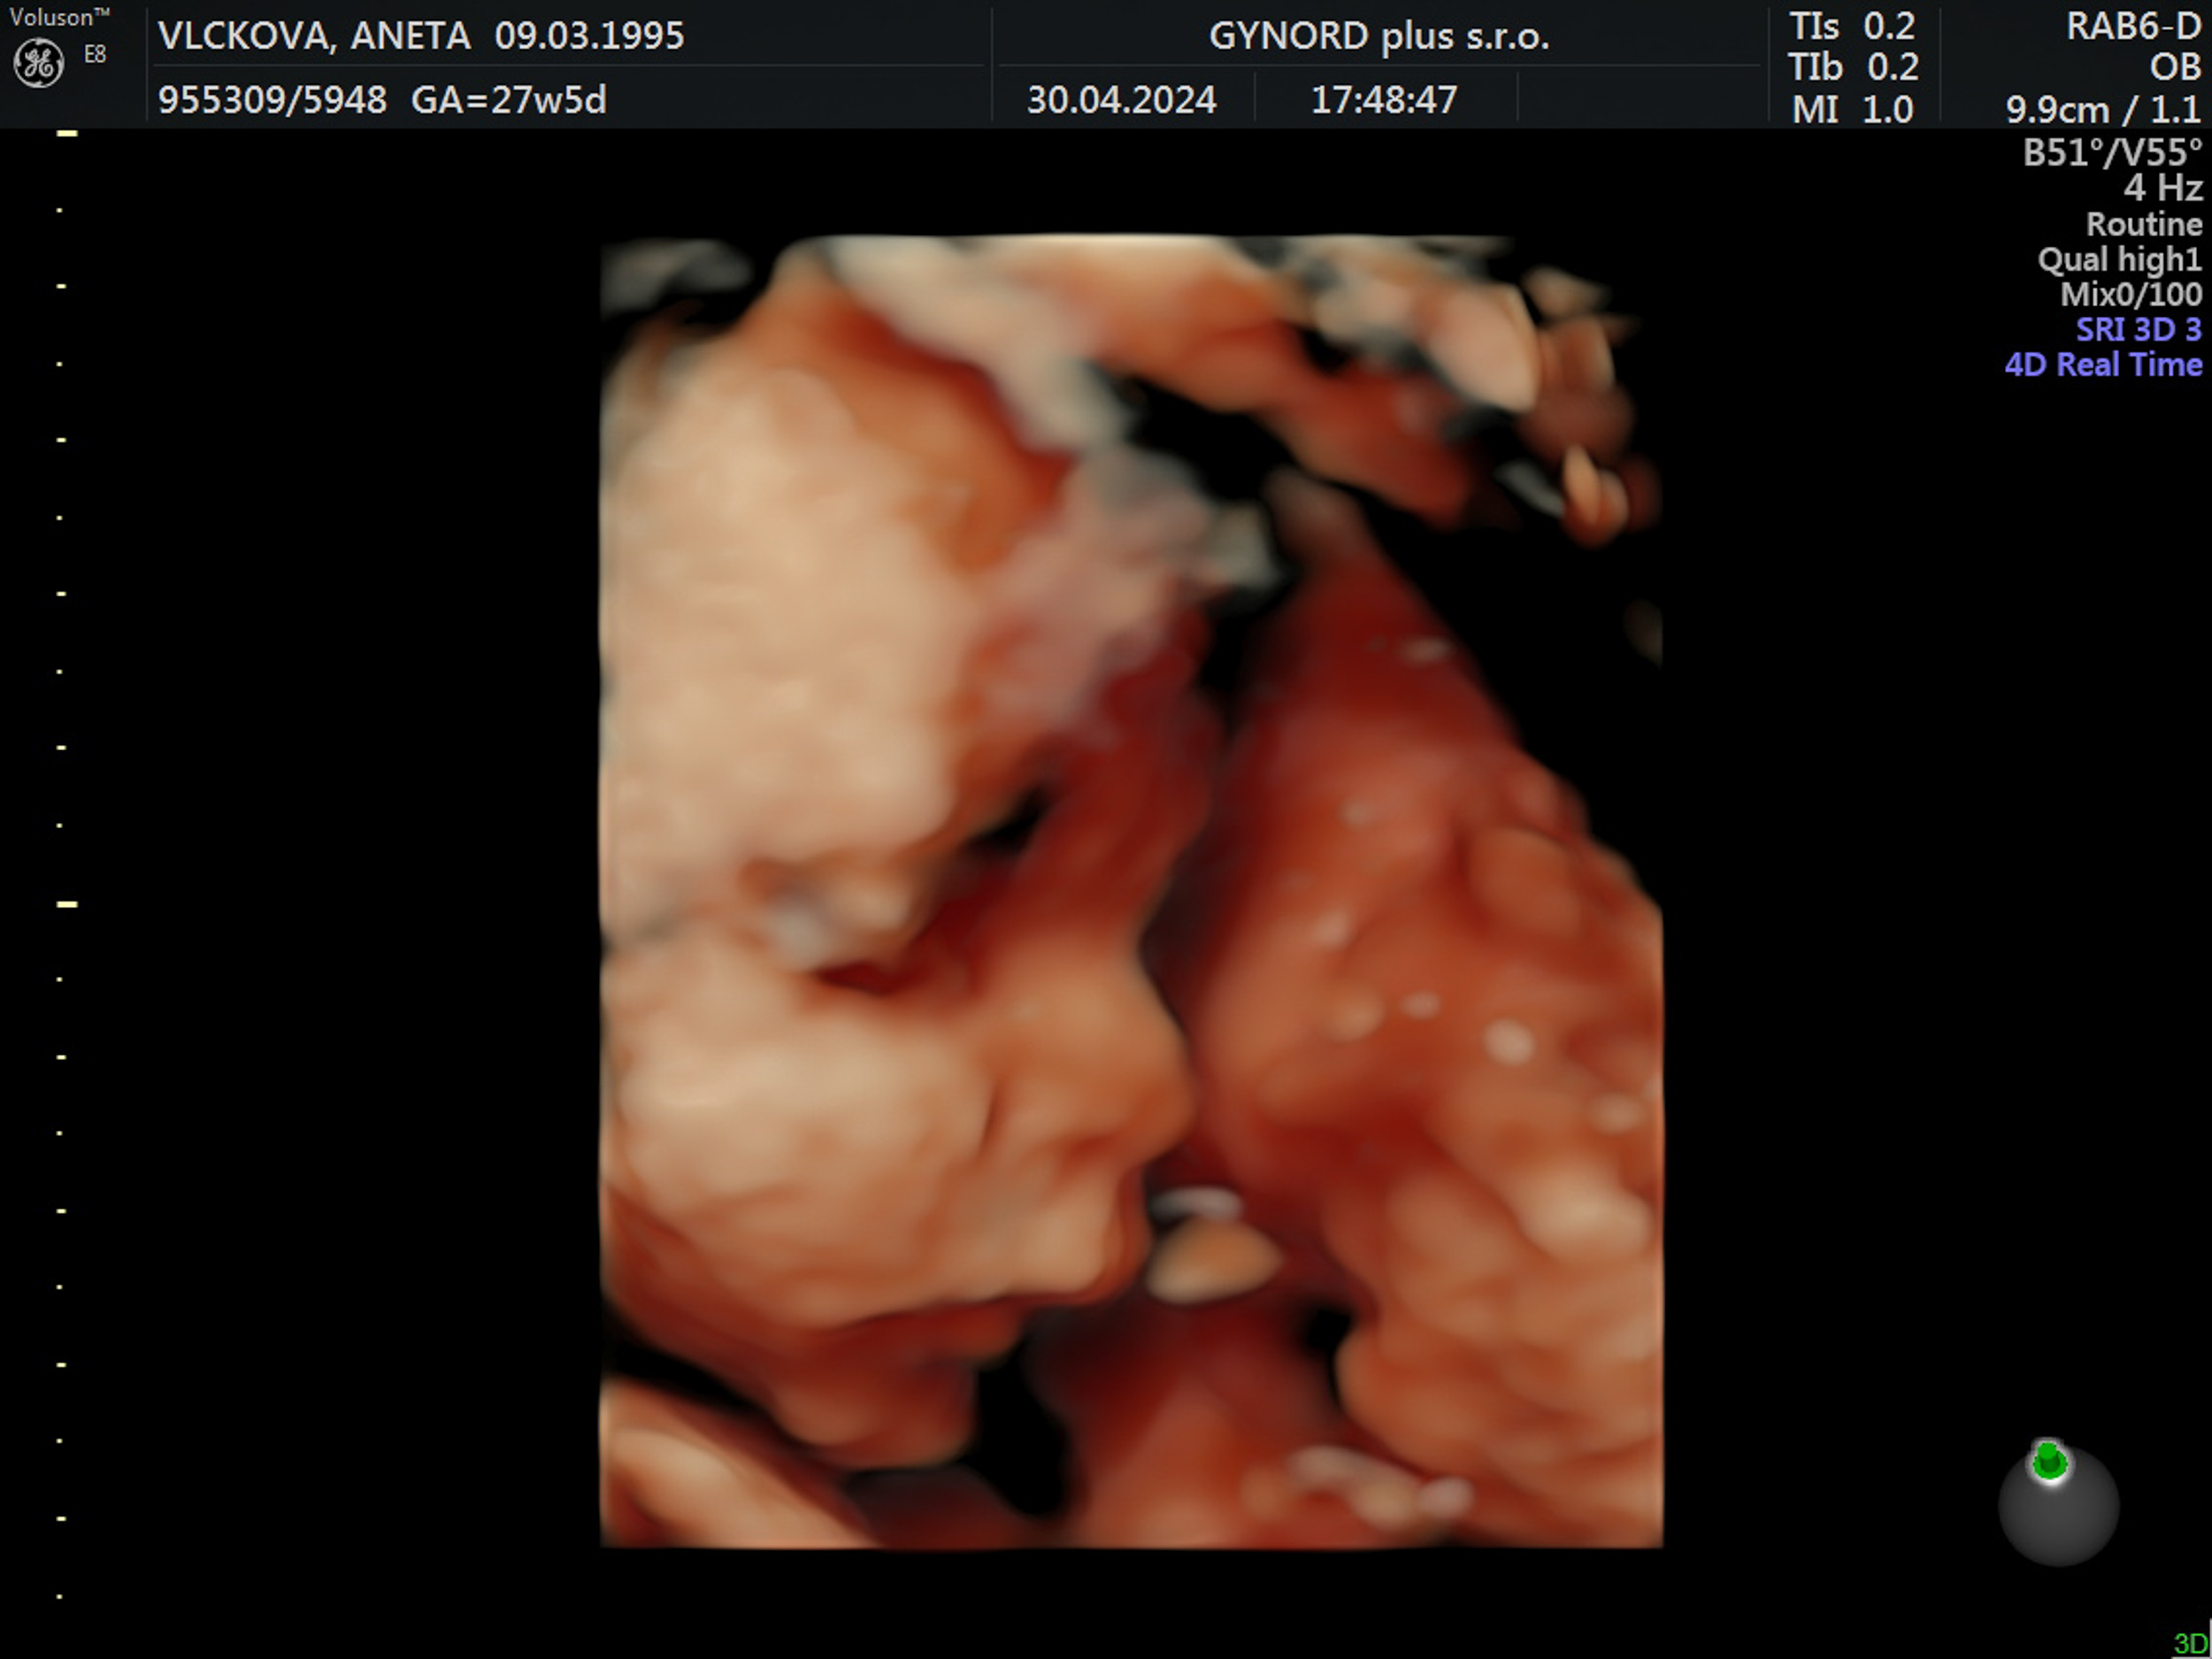

Tomášek - ještě v bříšku

2023-09-26